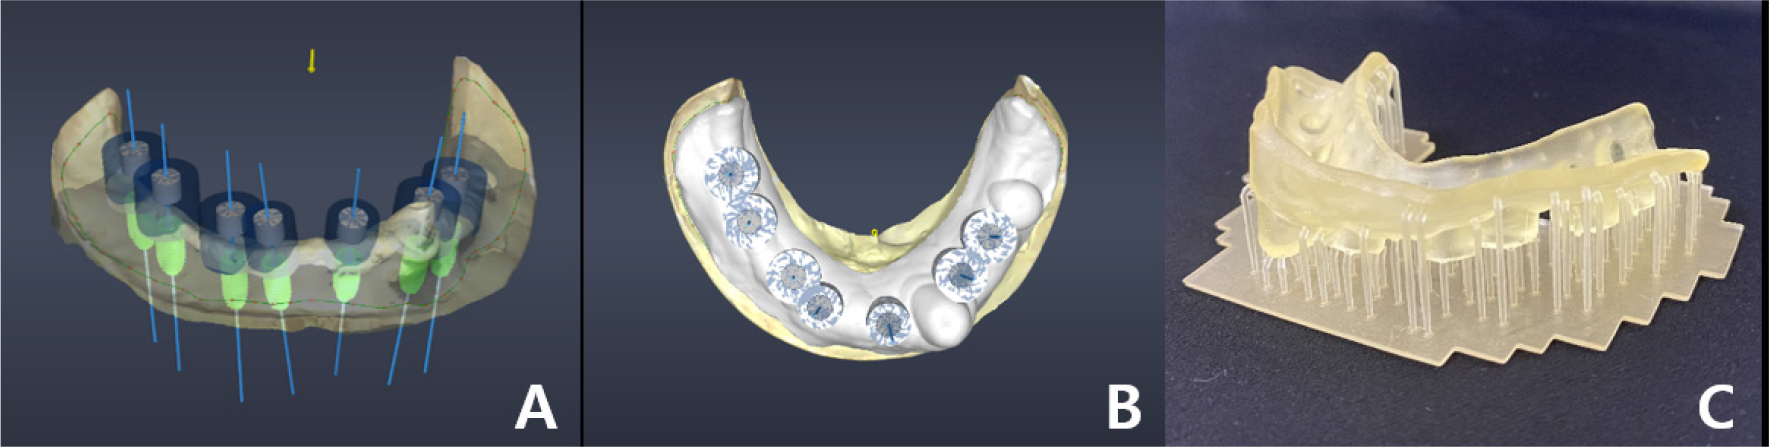

The model and CT scan data were superimposed using a dedicated software (DentiqGuide; 3D Industrial Imaging Co., Ltd., Seoul, Korea) for guided surgery and treatment planning. However, the mandibular arch had one tooth and one healing abutment on one side, which was not properly superimposed. Based on previous experience, it was thought that superimposition would be possible with 2-3 remaining teeth; therefore, the part where additional radiographic markers were not attached became a problem. To solve this problem, after applying powder (VITA powder scan spray; VITA Zahnfabrik H. Rauter GmbH & Co., KG, Bad Säckingen, Germany) to the radiographic stent and placing it on the stone model, an optical scan was performed to create another STL file (Fig. 3B and 3C).

DentalCAD 2.3 (Exocad GmbH; Darmstadt, Germany) program was used to superimpose radiographic stent model scan data with model scan data, and then both files were loaded on DentiqGuide software. DICOM files from CBCT data and radiographic stent model scan data were superimposed on DentiqGuide software using gutta-percha (Temporary stopping; GC Corporation, Tokyo, Japan) to match the model scan data with CBCT data (Fig. 4). In addition, to confirm that the model scan data and CBCT data matched accurately, we checked whether the gingiva line of the model and the bone line of CBCT matched the software and whether the location of the gutta-percha in the model and CBCT matched (Fig. 5). Implant planning and surgical guide design were performed by referring to the CBCT and model scan data, and the surgical guide was printed using a DLP (Digital Light Processing) type 3D printer (Zenith D; Dentis, Daegu, Korea) (Fig. 6). The lower left canine root is tilted mesially. Therefore, when working with the planning software, placing the implant on the adjacent lateral incisor was difficult, and the cantilever was planned after placement on the central incisor.